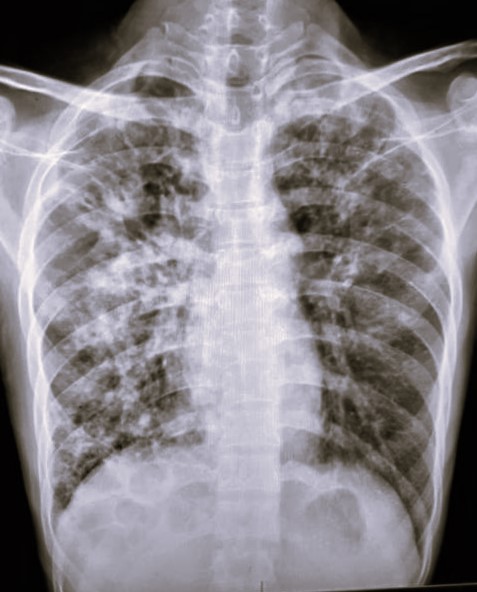

| 123 | IGGMC, Nagpur, Nagpur | P2 | 29-4349 | Dhammadip Wasnik | Consent taken on Paper | 35 Yrs. |

Provisional Diag : PTB Follow-up

Final Diag : Pulmonary Tuberculosis (Microbiologically Confirmed PTB) |

TB Case (Confirmed) | Abnormality visible on x-ray |